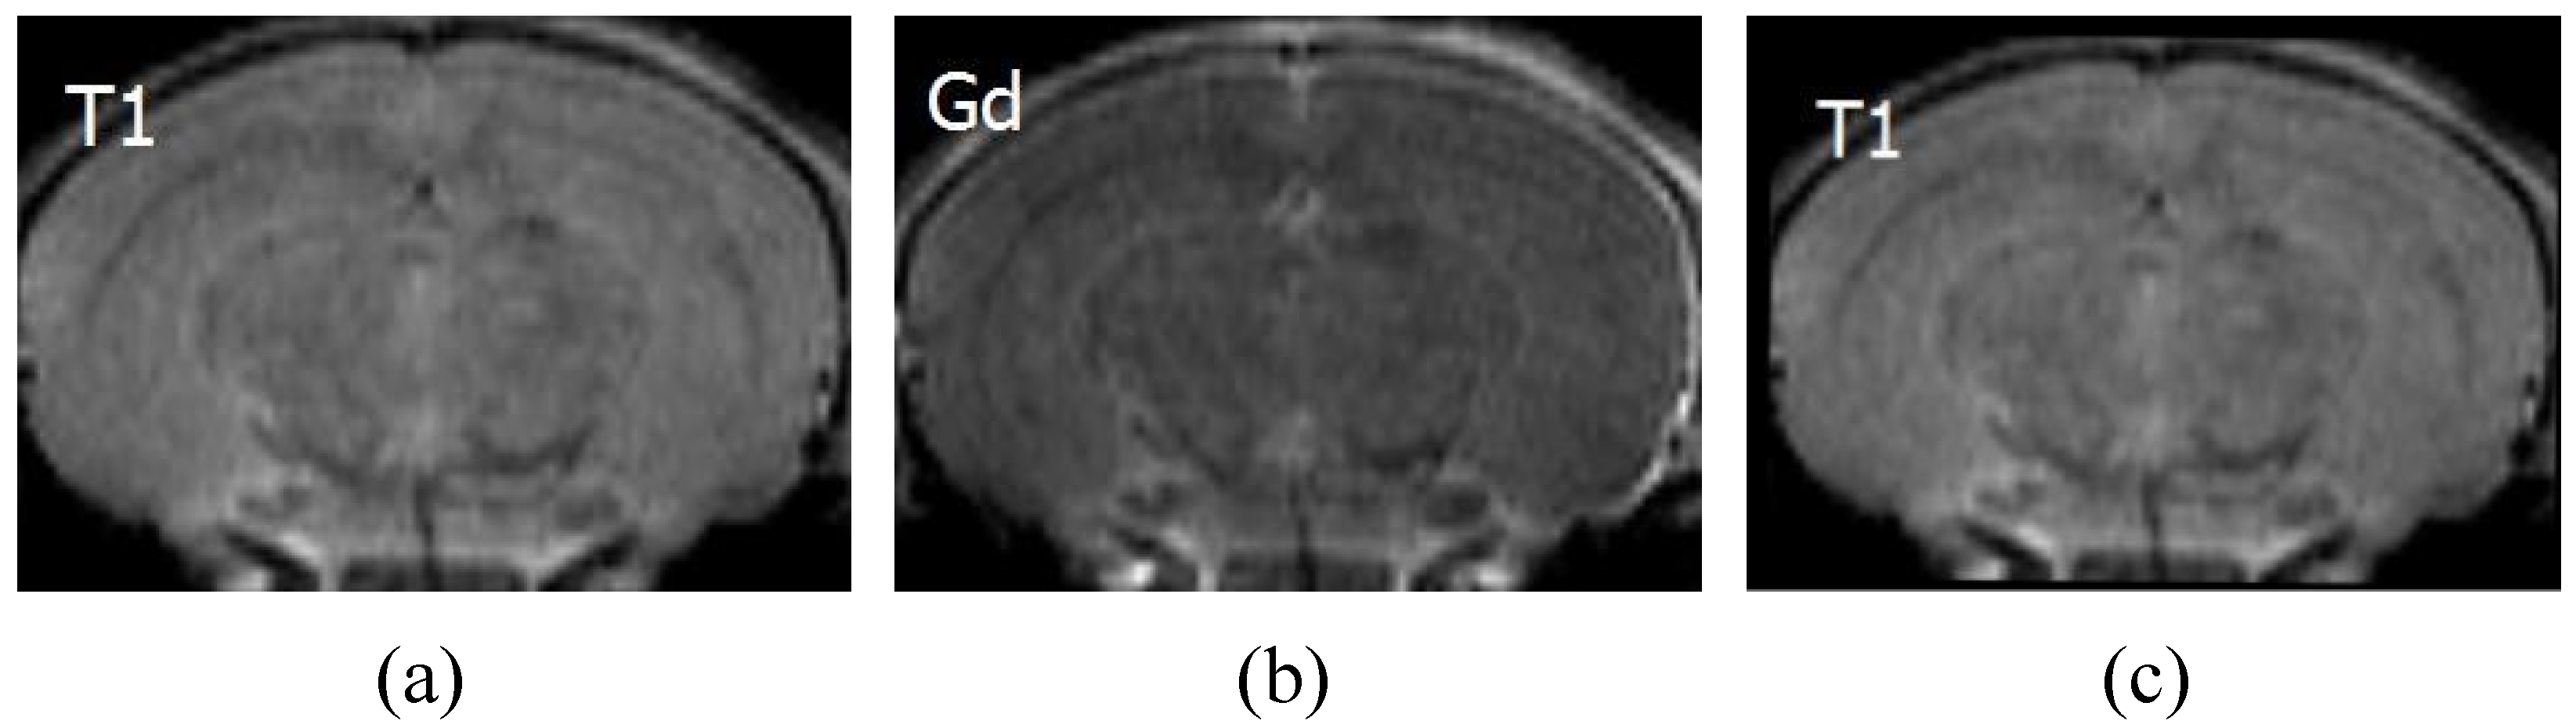

5. Applications

The feasibility of applying IFSrNet to other multimodal image registration tasks has been tried in medical images [47]. Chemical exchange saturation transfer (CEST) is a magnetic resonance imaging (MRI) technique for enhancing the contrast of images, which indirectly identifies the metabolites in tissue at millimolar concentrations through the water proton signal. Because the samples must have a sufficient saturation frequency, a large time span is usually required to acquire the spectrum. It is important to note that subject movement throughout the scan can lead to errors in CEST quantification. Even minor movements can have a significant impact on CEST analysis, resulting in the appearance of unusual peaks or dips in the spectrum and an uneven signal distribution on the image. To mitigate motion artefacts, image registration is a commonly employed method to ensure high-quality CEST-MRI images. Figure 15 shows the application of IFSrNet for registering T1 and Gd image pairs in CEST-MRI images of a rat brain. The lack of an objective gold standard for assessing the registration results of medical images means that the physician’s judgement is crucial. After observation by senior experts, IFSrNet was able to accurately reconstruct the target images, which illustrates the potential of the network’s application. All the CEST-MRI images in this experiment were obtained from Johns Hopkins University.

Figure 15. CEST-MRI images for a rat stroke lesion in which (a) is T1 as the image registration to be registered, (b) is Gd as the reference, and (c) is the T1 image that has been registered.